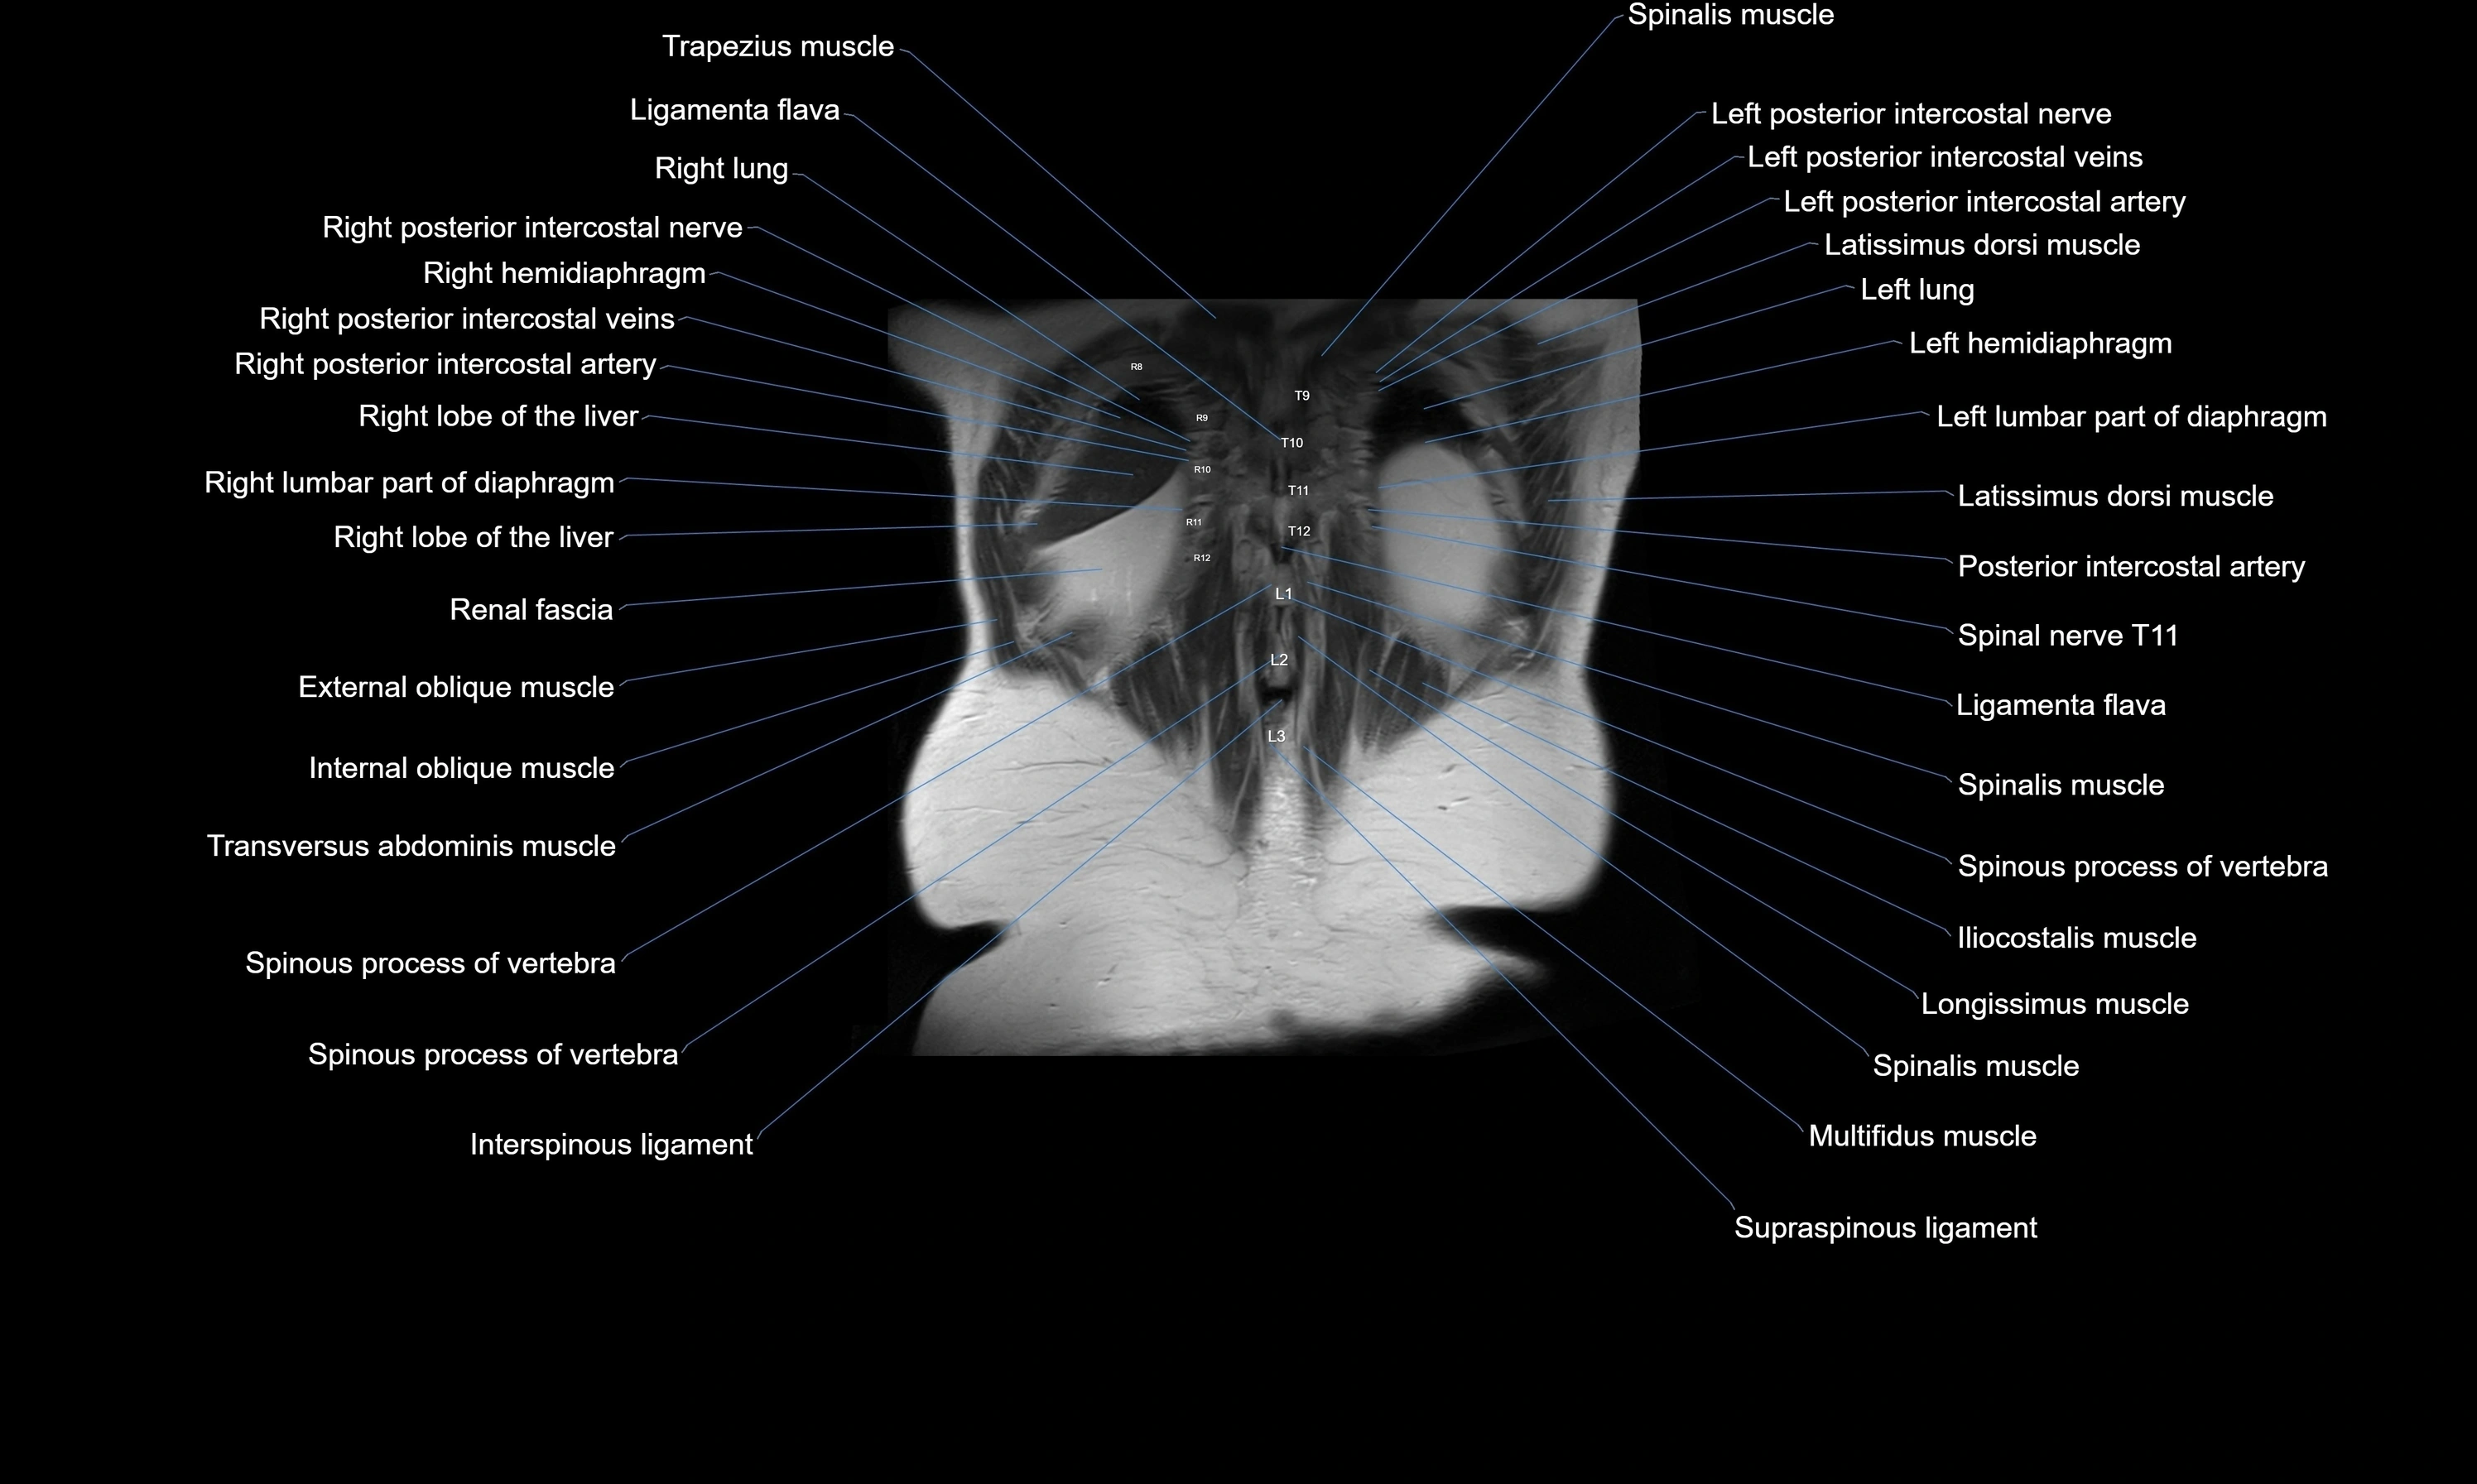

- External oblique muscle

- Internal oblique muscle

- Interspinous ligament

- Latissimus dorsi muscle

- Left hemidiaphragm

- Left lumbar part of diaphragm

- Ligamenta flava (Ligamentum flavum)

- Longissimus thoracis muscle

- Posterior intercostal arteries

- Posterior intercostal veins

- Serratus posterior inferior muscle

- Spinalis thoracis muscle

- Spinous process of vertebra

- Supraspinous ligament

- Transversus abdominis muscle